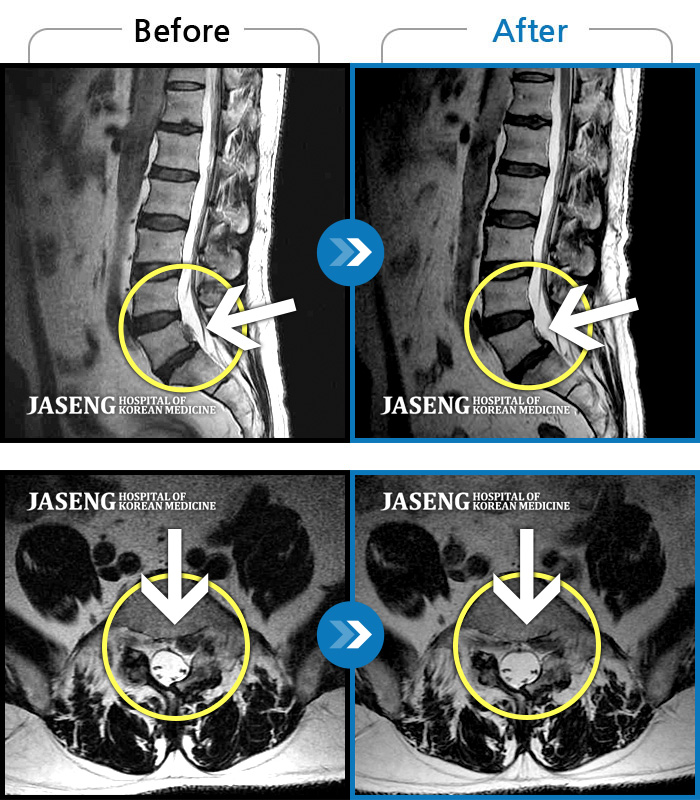

Before

After

환자에게 사전 동의를 받아 동일 조건에서 촬영되었습니다.

개인에 따라 치료 후 부작용이 발생할 수 있으니 의료진과 상담 후 치료를 진행하시기 바랍니다.